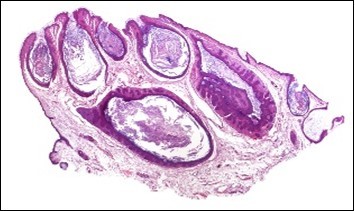

A cogent tissue specimen demonstrates typical features of comedones as follicular ostia distended and impacted with keratin. Significant histological manifestations are the occurrence of enlarged, grouped, distended follicular ostia demonstrating an absence of hair shafts along with impaction of laminated keratin. Base of the follicular invaginations may or may not delineate singular, rudimentary glandular structures. Miniature cysts, cystic invaginations and occasional enlarged cysts can be encountered. Cystic articulations are diverse and preponderantly layered by keratinizing, stratified squamous epithelium. Hyperkeratosis or epidermolytic hyperkeratosis and acanthosis of superimposed epidermis can concur although the lesion is devoid of parakeratosis or dyskeratosis5, 6.

Nevus comedonicus demonstrates immune reactivity to cytokeratin, simulating the expression of normal cutaneous surfaces. Generally encountered within the granular epidermal layer, immune reactivity for filaggrin is demonstrable within the entire epidermal thickness of closed comedones, a molecular which can be implicated in the genesis of nevus comedonicus6, 7. Electron microscopy demonstrates an enhanced quantification of Langerhans cells, numerous kerato-hyaline granules along with an abundance of tonofilaments within upper portion of stratum spinosum. Incompletely differentiated arrector pili muscles are impacted with intracellular glycogen particles6, 7. Figure 1, Figure 2, Figure 3, Figure 4, Figure 5, Figure 6, Figure 7, Figure 8, Figure 9, Figure 10.

Figure 3.Nevus comedonicus with aggregated follicular ostia, lamellated keratin, hyperkeratotic stratified squamous epithelial lining and an attenuated superimposed epithelium12.

Figure 4.Nevus comedonicus with distended follicular ostia, keratin accumulation, hyperkeratotic epithelial lining and intervening loose fibro-connective tissue13.